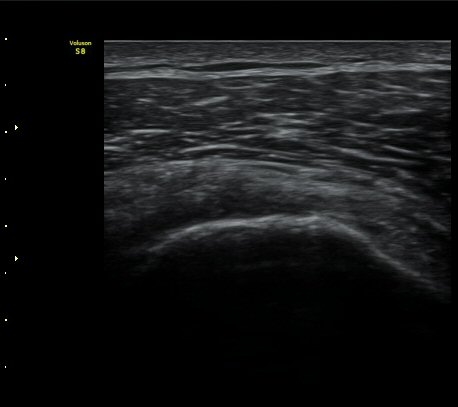

°ß°©ÇÏ±Ù°Ç ÁߺΠȾ´Ü¸é°Ë»ç»ó °ß°©Çã±Ù°ÇÀÌ ¾ã¾ÆÁö°í Á¡¾×³¶³» ¼ö¾×Àú·ù°¡ °üÂûµÊ

(±×¸² 8, 9).